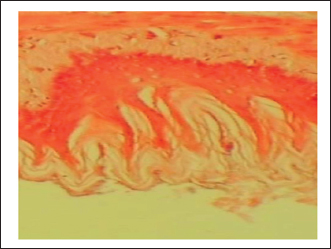

The gastric tissue slides were examined under a microscope for morphological changes such as hyperemia, hemorrhage, edema, necrosis, inflammatory changes, distortion, erosion, and ulcers caused by the destructive effects of indomethacin on stomach tissues. No pathological changes were observed in the normal control group (Fig. 1). Rats in the ulcer control group showed significant damage to the surface epithelium, necrotic areas penetrating the mucosal layer, and severe edema of the submucosal layer. Additionally, there was congestion with infiltration of inflammatory cells (Fig. 2). Histological results revealed that the treated rats with ranitidine had less protection of the gastric lining due to mild infiltration of leucocyte and edema in the submucosal layer, in addition to less disruption in both the superficial and deep mucosal layers. Treatment doses (300, 400 and 500 mg/kg) with P. farcta extract. Groups treated with P. farcta extract (300 and 400 mg/ kg) showed mild infiltration of inflammatory cells, edema, or significant disruption of the deep mucosa (Figs 5 and 6) while, P. farcta extract group (500mg/ kg) prevented histological changes and showed no infiltration of inflammatory cells, edema, or significant disruption of the deep mucosa (Figs 3, 4 and 7).

Fig. 3. Ulcer control group damage (↗) to the epithelium, necrotic areas penetrating the mucosal layer, and (↗) severe edema of the sub-mucosal layer with congestion and (↗) infiltration of inflammatory cells

The histopathological changes of gastric ulcer induction in the indomethacin (ulcer group) revealed the loss of epithelial layers, mucosal injury, decreased mucosal thickness with inflammatory cells infiltration and the distortion of mucosa and its glands. The ulcer initiation by indomethacin was accomplished on empty stomach via withholding food 12 hour before the induction later it has been revealed that the administration timing lead to gastric mucosal lesions which increased due to food that has buffering capacity against indomethacin effect. Also, the acute ulceration by lowering circulating prostaglandin levels and blocking COX (Jawad, 1976; Byeon et al., 2018). Prosopis farcta have been discovered the presence of resins, carbohydrates, alkaloids, flavonoids, phenols, tannins, saponins, coumarins, terpenes, and glycosides (Sharifi, 2019; Zughayyar and Gyad, 2023)